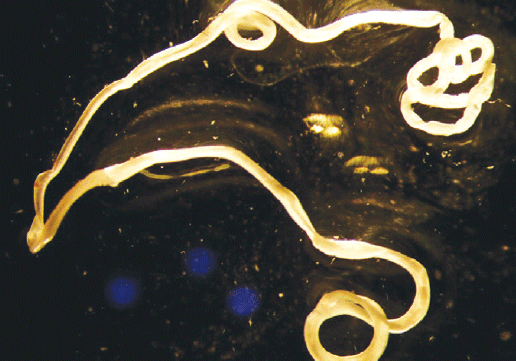

Fig. 5. Photo of the end area of the extracted D. repens female executed with a stereomicroscope digital camera

Рис. 5. Фото концевого отдела извлеченной самки D. repens, выполненноe цифровой камерой стереoмикроскопа

Fig. 6. Photo of a helminth executed with a stereomicroscope digital camera

Рис. 6. Фото гельминта, выполненноe цифровой камерой стереoмикроскопа